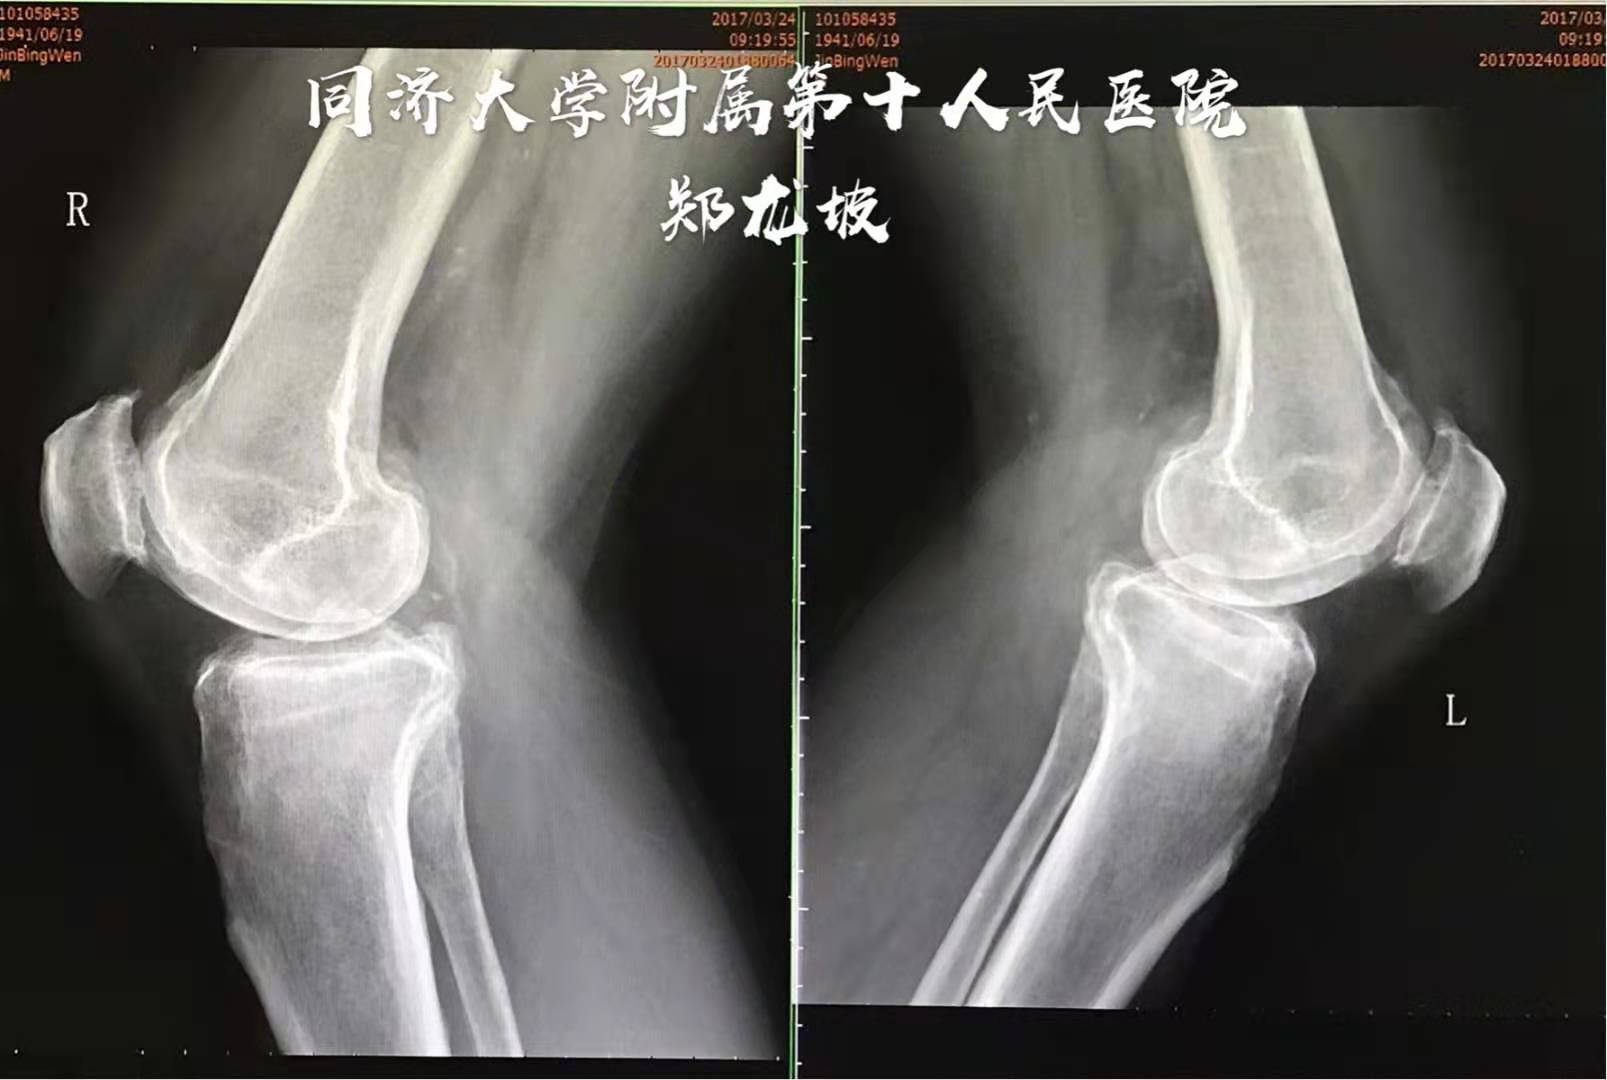

江苏宿迁慕名前来就诊的73岁男性患者,双膝关节骨性关节炎多年,上下楼及下蹲时困难且疼痛加剧,口服多种药物不能缓解症状,经朋友介绍来我专家门诊求诊。检查发现双膝被动屈曲超过90度后疼痛且不不能再屈。X光片显示膝关节内侧间隙变窄,髌股关节软骨磨损,双侧膝关节轻度内翻。

侧位X线显示髌骨关节磨损